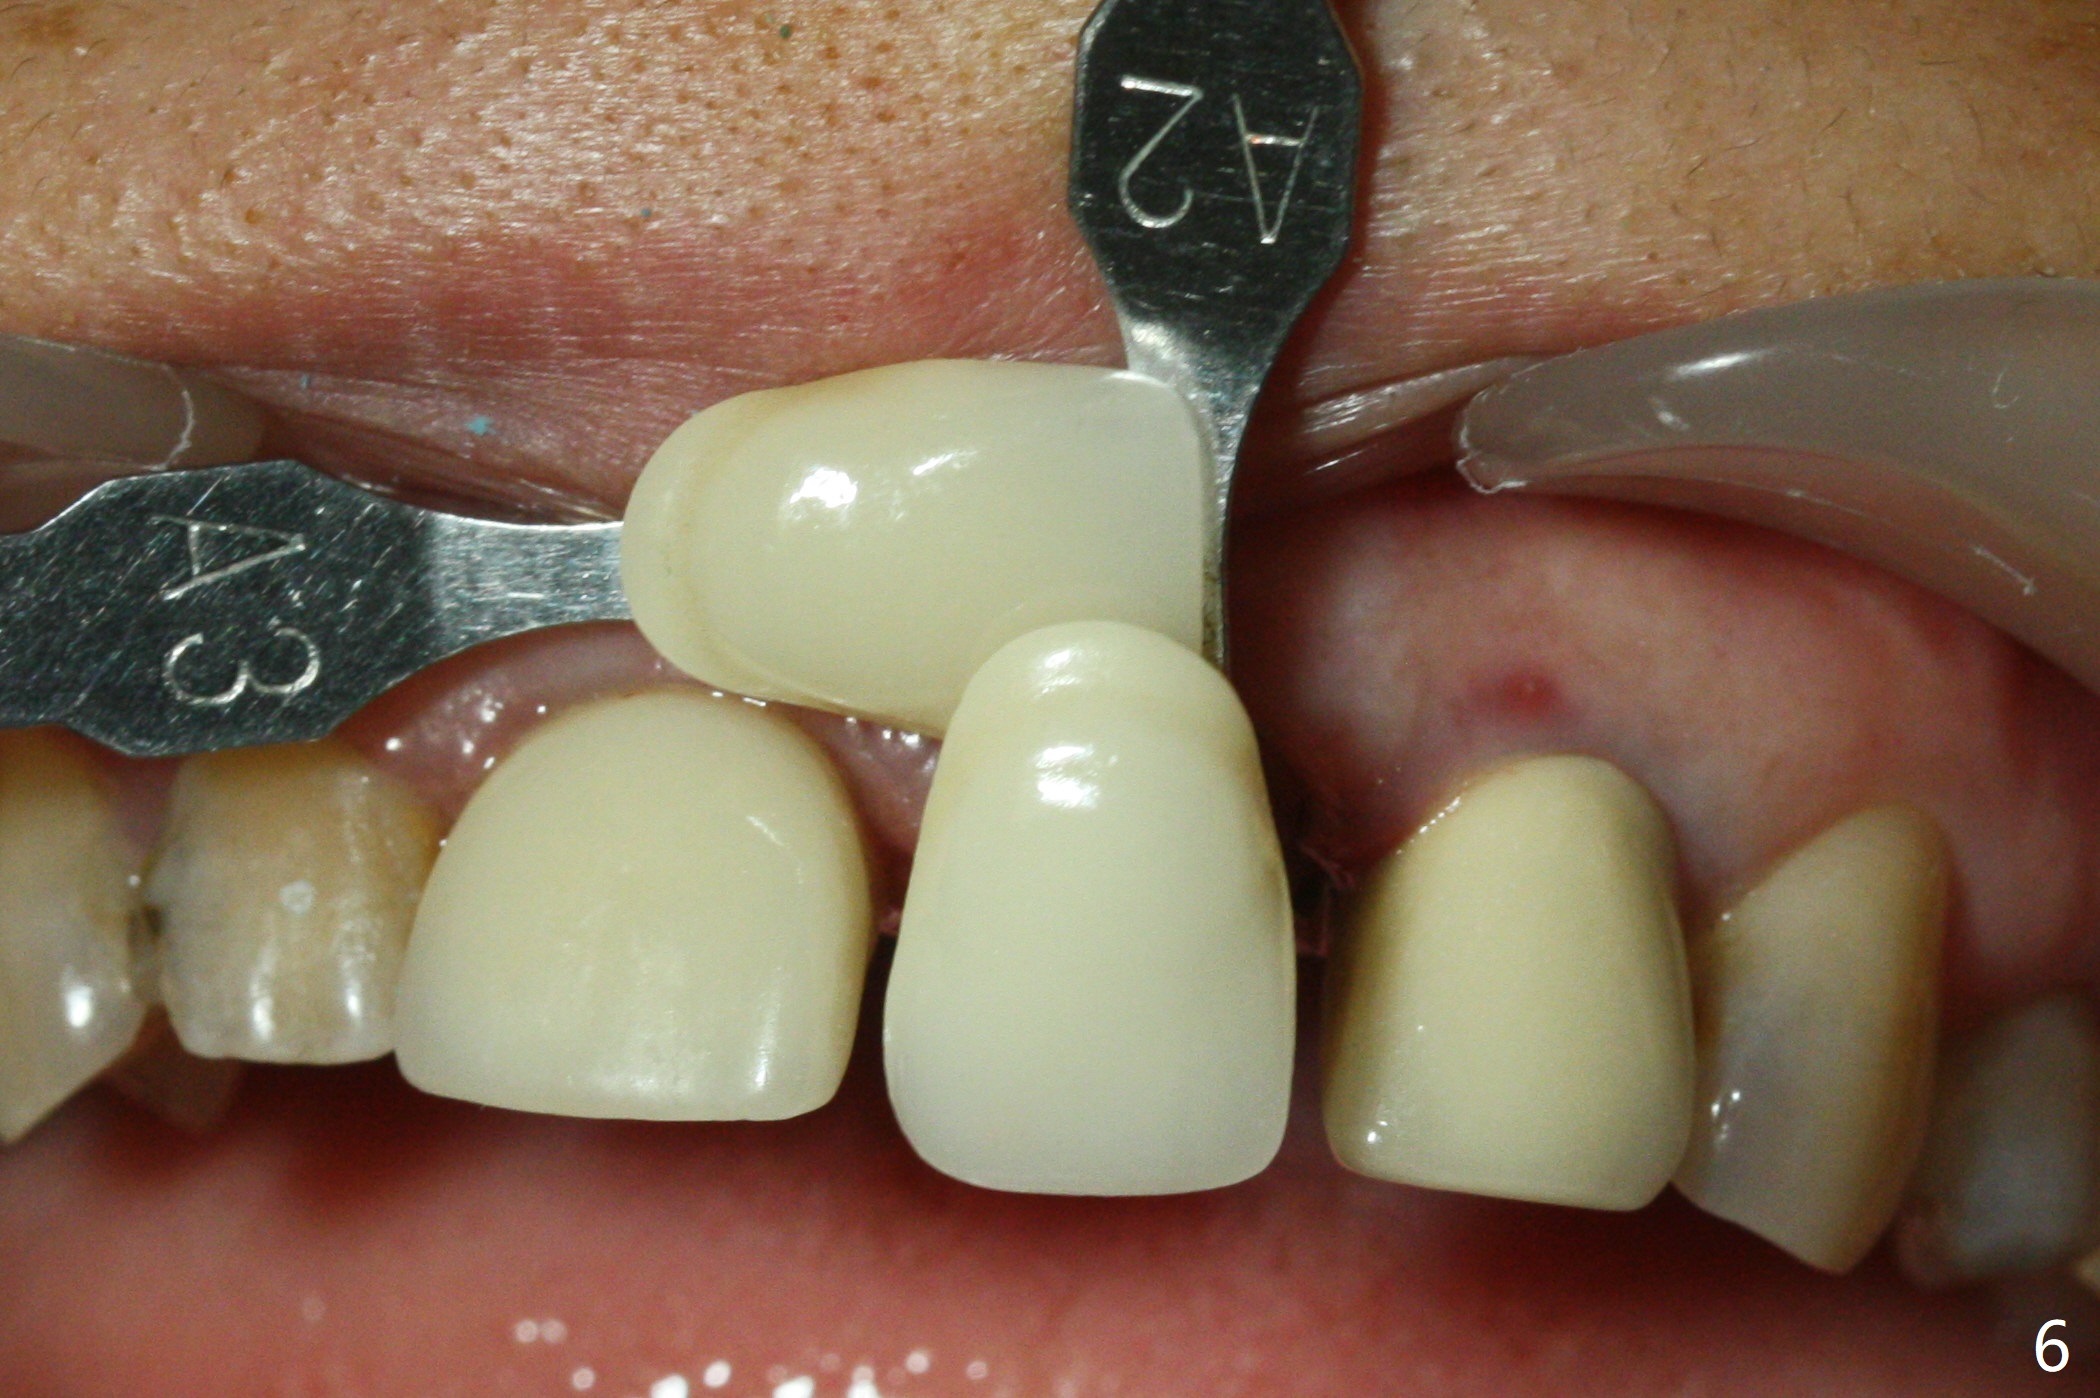

When the 44-year-old woman returns, the crown dislodges from #9 with palatal porcelain chip (Fig.1). Although the post is in place as compared to its dislodgement last visit, it is short and pointed (Fig.2,3 P). Because of the anterior deep bite (Fig.4), an implant restoration may not provide advantage; a new build-up is fabricated (B-U) for a new crown (Fig.5-6). The existing crown is reinserted for shade comparison (Fig.7 C). The gingiva at #8 and 9 is healthy, whereas that at #10 is not (Fig.8). PA taken 5 months later shows that the crown at #10 looks normal (Fig.9).